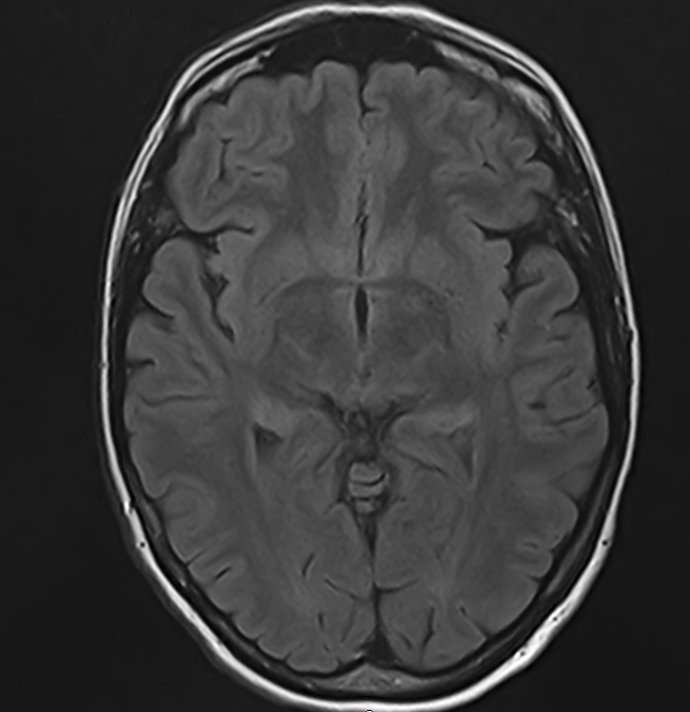

Стандартная МРТ головного мозга дает важную информацию о состоянии и структуре мозговой ткани для выявления большого числа заболеваний, в том числе опухолевых образований, демиелинизирующих заболеваний, воспалительных процессов головного мозга и мозговых оболочек. Стандартную МРТ головного мозга дополняет МР-ангиография, которая отображает состояние артериальной системы кровоснабжения головного мозга. МР-венография головного мозга позволяет детально изучить особенности анатомического и функциональной состояния венозного русла головного мозга.

Компьютерная программа обрабатывает данные, полученные при сканировании, и формирует объемные изображения как самого мозга, так и сосудистой системы в отдельности без прилегающих тканей. Обе методики применяются одновременно и взаимодополняют друг друга, давая полную диагностическую картину.